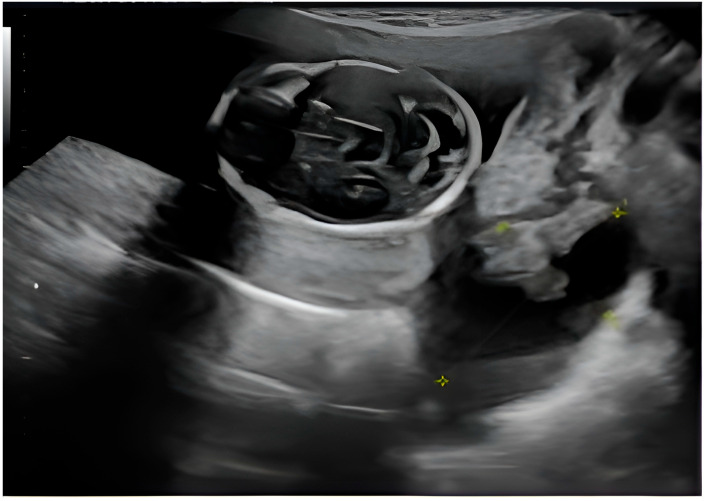

背景:息肉样子宫内膜异位症是一种罕见的子宫内膜异位症,表现为肿瘤肿块,很难与恶性肿瘤区分。它通常发生在围绝经期妇女或接受激素治疗的妇女中,在年轻孕妇中出现极为罕见。病例介绍:这篇文章描述了一个罕见的妊娠妇女的息肉样卵巢子宫内膜异位症,在医学文献中很少有记录的病例。在常规产前超声检查中偶然发现附件肿块,其影像学特征引起了肿瘤过程的怀疑,并提示手术排除恶性肿瘤。然而,切除病变的组织病理学检查证实了与息肉样子宫内膜异位症相符的特征,没有发现癌症的证据。本病例强调了鉴别子宫内膜异位症与卵巢肿瘤的诊断挑战,特别是在妊娠期间,影像学表现可能不明确。此外,妊娠期固有的激素环境可能加剧子宫内膜异位症病变的增殖行为,从而使临床评估复杂化。在这种情况下,附件肿块的存在通常需要仔细评估,以平衡手术风险和延迟诊断的潜在后果。提出的数据强调了准确诊断的重要性。最后,协调良好的做法可确保保护孕产妇和胎儿健康。结论:通过优先准确的诊断和个性化的治疗方案,医生可以最大限度地减少并发症,改善母亲和孩子的预后。

Background: Polypoid endometriosis is a rare variant of endometriosis that presents as a tumorous mass, making it difficult to differentiate it from a malignant tumor. It usually occurs in perimenopausal women or those undergoing hormone therapy, and its presence in a young pregnant woman is extremely uncommon. Case Presentation: This article describes a rare instance of polypoid ovarian endometriosis in a pregnant woman, a condition with few documented cases in the medical literature. An adnexal mass was discovered incidentally during a routine prenatal ultrasound, with imaging features that raised the suspicion of a neoplastic process and prompted surgery to exclude malignancy. However, histopathological examination of the excised lesion confirmed features compatible with polypoid endometriosis, without revealing evidence of cancer. This case highlights the diagnostic challenges of differentiating polypoid endometriosis from ovarian neoplasms, especially during gestation, where imaging findings can be ambiguous. In addition, the hormonal environment inherent in pregnancy may exacerbate the proliferative behavior of endometriotic lesions, thus complicating clinical evaluations. The presence of an adnexal mass in such a setting often requires careful evaluation to balance the risks of surgery with the potential consequences of delayed diagnosis. The data presented emphasize the importance of an accurate diagnosis. In conclusion, a well-coordinated approach ensures the protection of maternal and fetal health. Conclusions: By prioritizing accurate diagnosis and personalized treatment plans, physicians can minimize complications and improve outcomes for both mother and child.